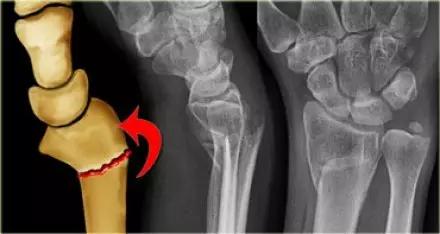

2. Colles 骨折

桡骨远端骨折,伴有桡骨远端向背侧的移位,可以有或没有尺骨干的骨折。具有这几个特征:背侧粉碎、向背侧成角、向背侧移位且挠骨短缩的关节外骨折。

典型 colles 骨折,枪刺样、餐叉样畸形